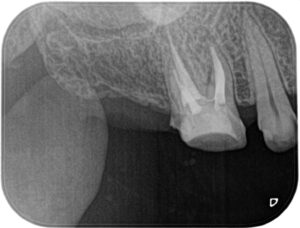

術中:顕微鏡を用いて破折器具は除去できましたが、近心根の根尖は初回の根管治療で大きく削られていました。保険の材料では十分に治療できないと判断し、MTAセメントを用いて根管充填を行うことにしました。

根管充填後:根尖まで緊密にMTAセメントで充填できました。